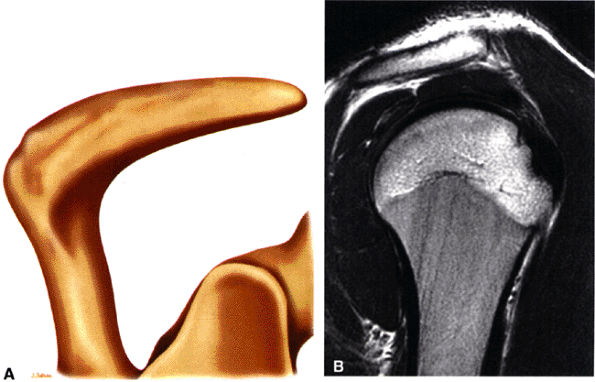

The acromion is classified into several types according to its morphology:

Type 1 (a flat or straight undersurface with a high angle of inclination)

Type 2 (a curved arc and decreased angle of inclination)

Type 3 (hooked anteriorly with a decreased angle of inclination)

Type 4 (upward convexity of the inferior surface) (see also the discussion of the etiology of shoulder impingement syndrome)